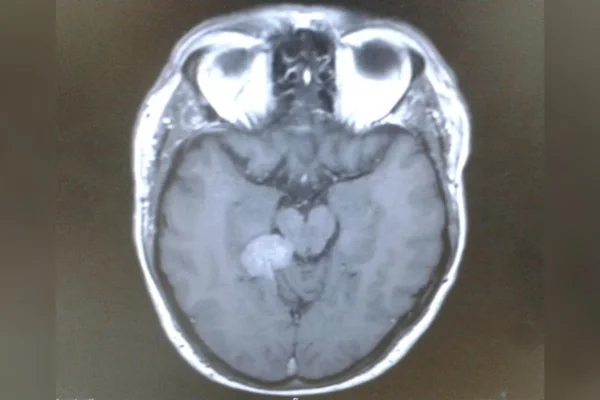

A confirmação veio em março de 2015. Após ser encaminhado a um neurocirurgião, Darren recebeu o diagnóstico de um meningioma tentorial em estágio inicial.

Trata-se de um tumor geralmente benigno e de crescimento lento, que se desenvolve a partir das meninges, as membranas que envolvem o cérebro. No caso dele, a lesão estava localizada na base do cérebro, em uma área considerada inoperável por causa dos riscos do procedimento.

Apesar de não ser canceroso, esse tipo de lesão pode causar uma série de sintomas ao pressionar estruturas cerebrais e nervos. Entre eles estão zumbido no ouvido, dores de cabeça, alterações na visão, perda auditiva, diminuição do olfato e dificuldade para engolir. Se não tratado, pode se tornar potencialmente fatal.

O meningioma é um tumor geralmente benigno, de crescimento lento, que se forma a partir das meninges, as membranas que envolvem o cérebro